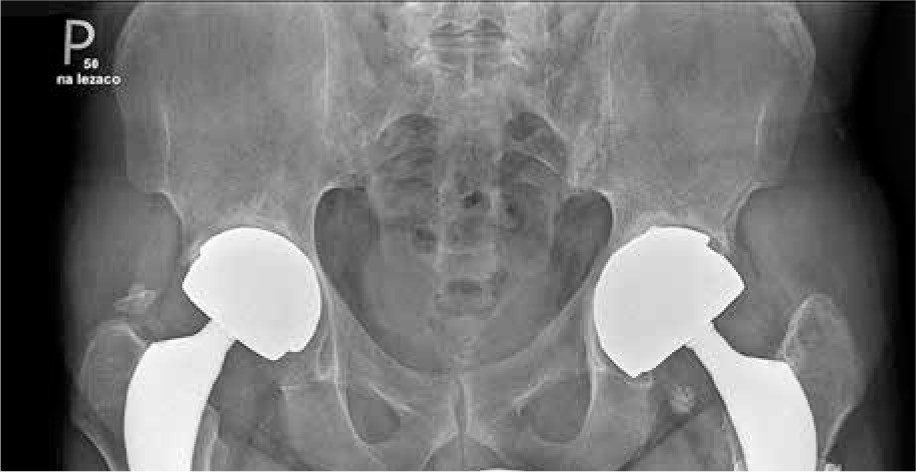

Fig. 2

X-ray of hands showing juxta-articular osteoporosis and inflammatory cysts. No erosions and joint space narrowing. Sharp/van der Heijde score = 0. Juxta-articular osteoporosis is a typical finding in hand X-ray in RA but rare in AS